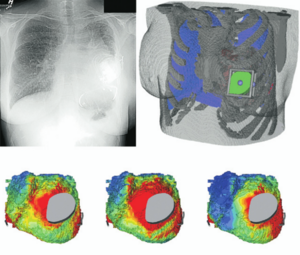

Treatment Planning and Delivery of Whole Brain Irradiation with Hippocampal Avoidance in Rats

Publication: PLoS One. 2015 Dec 4;10(12):e0143208. PMID: 26636762 | PDF Authors: Cramer CK, Yoon SW, Reinsvold M, Joo KM, Norris H, Hood RC, Adamson JD, Klein RC, Kirsch DG, Oldham M. Institution: Department of Radiation Oncology, Duke University Medical Center, Durham, NC, USA. Background/Purpose: Despite the clinical benefit of whole brain radiotherapy (WBRT), patients and physicians are concerned by the long-term impact on cognitive functioning. Many studies investigating the molecular and cellular impact of WBRT have used rodent models. However, there has not been a rodent protocol comparable to the recently reported Radiation Therapy Oncology Group (RTOG) protocol for WBRT with hippocampal avoidance (HA) which is intended to spare cognitive function. The aim of this study was to develop a hippocampal-sparing WBRT protocol in Wistar rats. Methods: The technical and clinical challenges encountered in hippocampal sparing during rat WBRT are substantial. Three key challenges were identified: hippocampal localization, treatment planning, and treatment localization. Hippocampal localization was achieved with sophisticated imaging techniques requiring deformable registration of a rat MRI atlas with a high resolution MRI followed by fusion via rigid registration to a CBCT. Treatment planning employed a Monte Carlo dose calculation in SmART-Plan and creation of 0.5 cm thick lead blocks custom-shaped to match DRR projections. Treatment localization necessitated the on-board image-guidance capability of the XRAD C225Cx micro-CT/micro-irradiator (Precision X-Ray). Treatment was accomplished with opposed lateral fields with 225 KVp X-rays at a current of 13mA filtered through 0.3 mm of copper using a 40x40 mm square collimator and the lead blocks. A single fraction of 4Gy was delivered (2Gy per lateral field) with a 41 second beam on time per field at a dose rate of 304.5 cGy/min. Dosimetric verification of hippocampal sparing was performed using radiochromic film. In vivo verification of HA was performed after delivery of a single 4Gy fraction either with or without HA using γ-H2Ax staining of tissue sections from the brain to quantify the amount of DNA damage in rats treated with HA, WBRT, or sham-irradiated (negative controls). Results: The mean dose delivered to radiochromic film beneath the hippocampal block was 0.52Gy compared to 3.93Gy without the block, indicating an 87% reduction in the dose delivered to the hippocampus. This difference was consistent with doses predicted by Monte Carlo dose calculation. The Dose Volume Histogram (DVH) generated via Monte Carlo simulation showed an underdose of the target volume (brain minus hippocampus) with 50% of the target volume receiving 100% of the prescription isodose as a result of the lateral blocking techniques sparing some midline thalamic and subcortical tissue. Staining of brain sections with anti-phospho-Histone H2A.X (reflecting double-strand DNA breaks) demonstrated that this treatment protocol limited radiation dose to the hippocampus in vivo. The mean signal intensity from γ-H2Ax staining in the cortex was not significantly different from the signal intensity in the cortex of rats treated with WBRT (5.40 v. 5.75, P = 0.32). In contrast, the signal intensity in the hippocampus of rats treated with HA was significantly lower than rats treated with WBRT (4.55 v. 6.93, P = 0.012). Conclusion: Despite the challenges of planning conformal treatments for small volumes in rodents, our dosimetric and in vivo data show that WBRT with HA is feasible in rats. This study provides a useful platform for further application and refinement of the technique. Funding:

MRI with labeled structures from atlas registered to the CBCT. Registration was carried out with the open source imaging tool 3D Slicer, Version 4.4.0. |